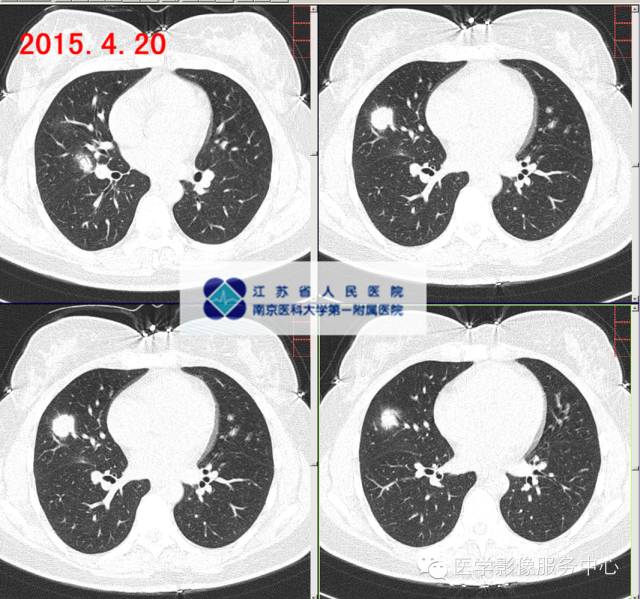

影像分析:右中肺多发病灶,较大病灶较2015-03-21片变实,感染?COP?建议穿刺活检明确病灶性质。

影像分析:右肺中叶多发病灶,较大病灶较2015-03-27片增大、变实,考虑为CA?感染?COP?建议穿刺活检明确病灶性质。